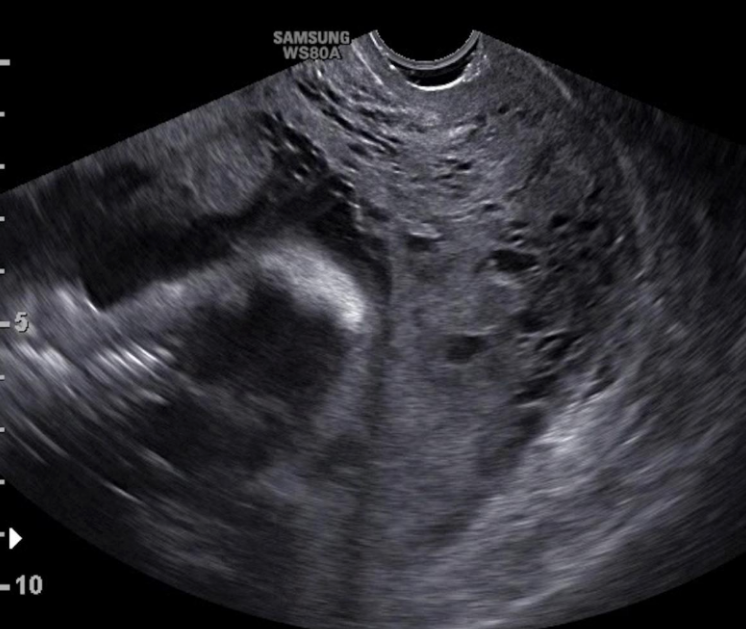

Qua siêu âm có thể phát hiện được tình trạng rau cài răng lược, nhưng chỉ có thể phát hiện trong 3 tháng cuối trong thai kỳ.

Đây là giai đoạn rất quan trọng cần đặc biệt chú ý, lúc này các bác sĩ có thể dễ dàng kiểm tra tình trạng của rau thai, có thể phát hiện được nếu các gai rau bám quá sâu, từ đó, có thể đưa ra các phương án khắc phục kịp thời.

Hình ảnh rau cài răng lược trên siêu âm vào quý 2, 3 thai kỳ sẽ cho biết các dấu hiệu như:

Tuy nhiên, không phải trường hợp nào cũng có thể phát hiện được rau cài răng lược trên siêu âm trong vòng 3 tháng cuối và xử lý ngay, mà chỉ phát hiện rau thai không bóc tách được sau khi sinh. Do đó, trước khi sinh nở, bạn cần tìm đến cơ sở y tế uy tín để đảm bảo an toàn về sức khỏe của cả mẹ và bé.